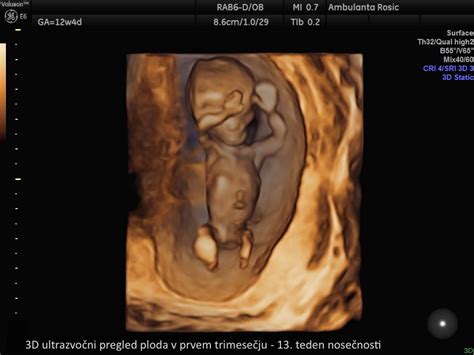

- 11. in 12. teden: Glava zavzema polovico velikosti ploda. Razvijejo se očesne veke in zametki zob. Formirajo se jetra in zunanje genitalije, nastanejo nohti. Plod meri v dolžino 4-5 cm. Od 11. tedna dalje je možno opraviti ultrazvočno merjenje nuhalne svetline. Nastanek organov je v 12. tednu v največji meri zaključen. Prebavila so v 12. tednu že v trebušni votlini. Posteljica plod že lahko oskrbuje s hrano in kisikom. Po 11. tednu je konec kritičnega obdobja. V 11. tednu je plod velik od 44 do 60 milimetrov in težek nekje 8 gramov. Tu nekje je konec kritičnega obdobja za možnost spontanega splava. Glava zavzema polovico telesa, takrat že zeha, požira, razvijejo se tudi nohti in dlačice, razviti so življenjsko pomembni organi, jetra, ledvice, črevesje, možgani in pljuča so razviti že v celoti in delujejo. Do konca nosečnosti morajo samo še rasti in dozoreti. V 12. tednu je plod velik 61 milimetrov, težek od 8 do 14 gramov, razvit je od glave do pete, rastejo mu že lasje in nohti, razvijejo se glasilke, žleza hipofiza, premika že roke, prste na dlaneh, stopalih, se smeji in sesa svoj palec. Posteljica pa že takrat začne skrbeti za pretok med maternico in otročkom.

- 13. in 14. teden: Na prstih se pričnejo razvijati prstni odtisi. Razvile so se zasnove za vseh 20 mlečnih zob. Trebušna slinavka prične izločati inzulin. Na ultrazvočnem pregledu je že mogoče določiti spol. Plod v 13. tednu meri približno 7 cm in tehta približno 20 gramov. Opazni so dihalni gibi, plod požira plodovnico in izloča urin. Koža je poraščena z mehkimi lanugo dlačicami. V tem obdobju je plod še zelo ranljiv, zato je izogibanje škodljivim dejavnikom še vedno ključnega pomena. Do 12. tedna je tisto kritično obdobje, do kadar je možen spontani splav, zato je res priporočljivo, da se v tem času ženske izogibajo vsem tem rizičnim dejavnikom.